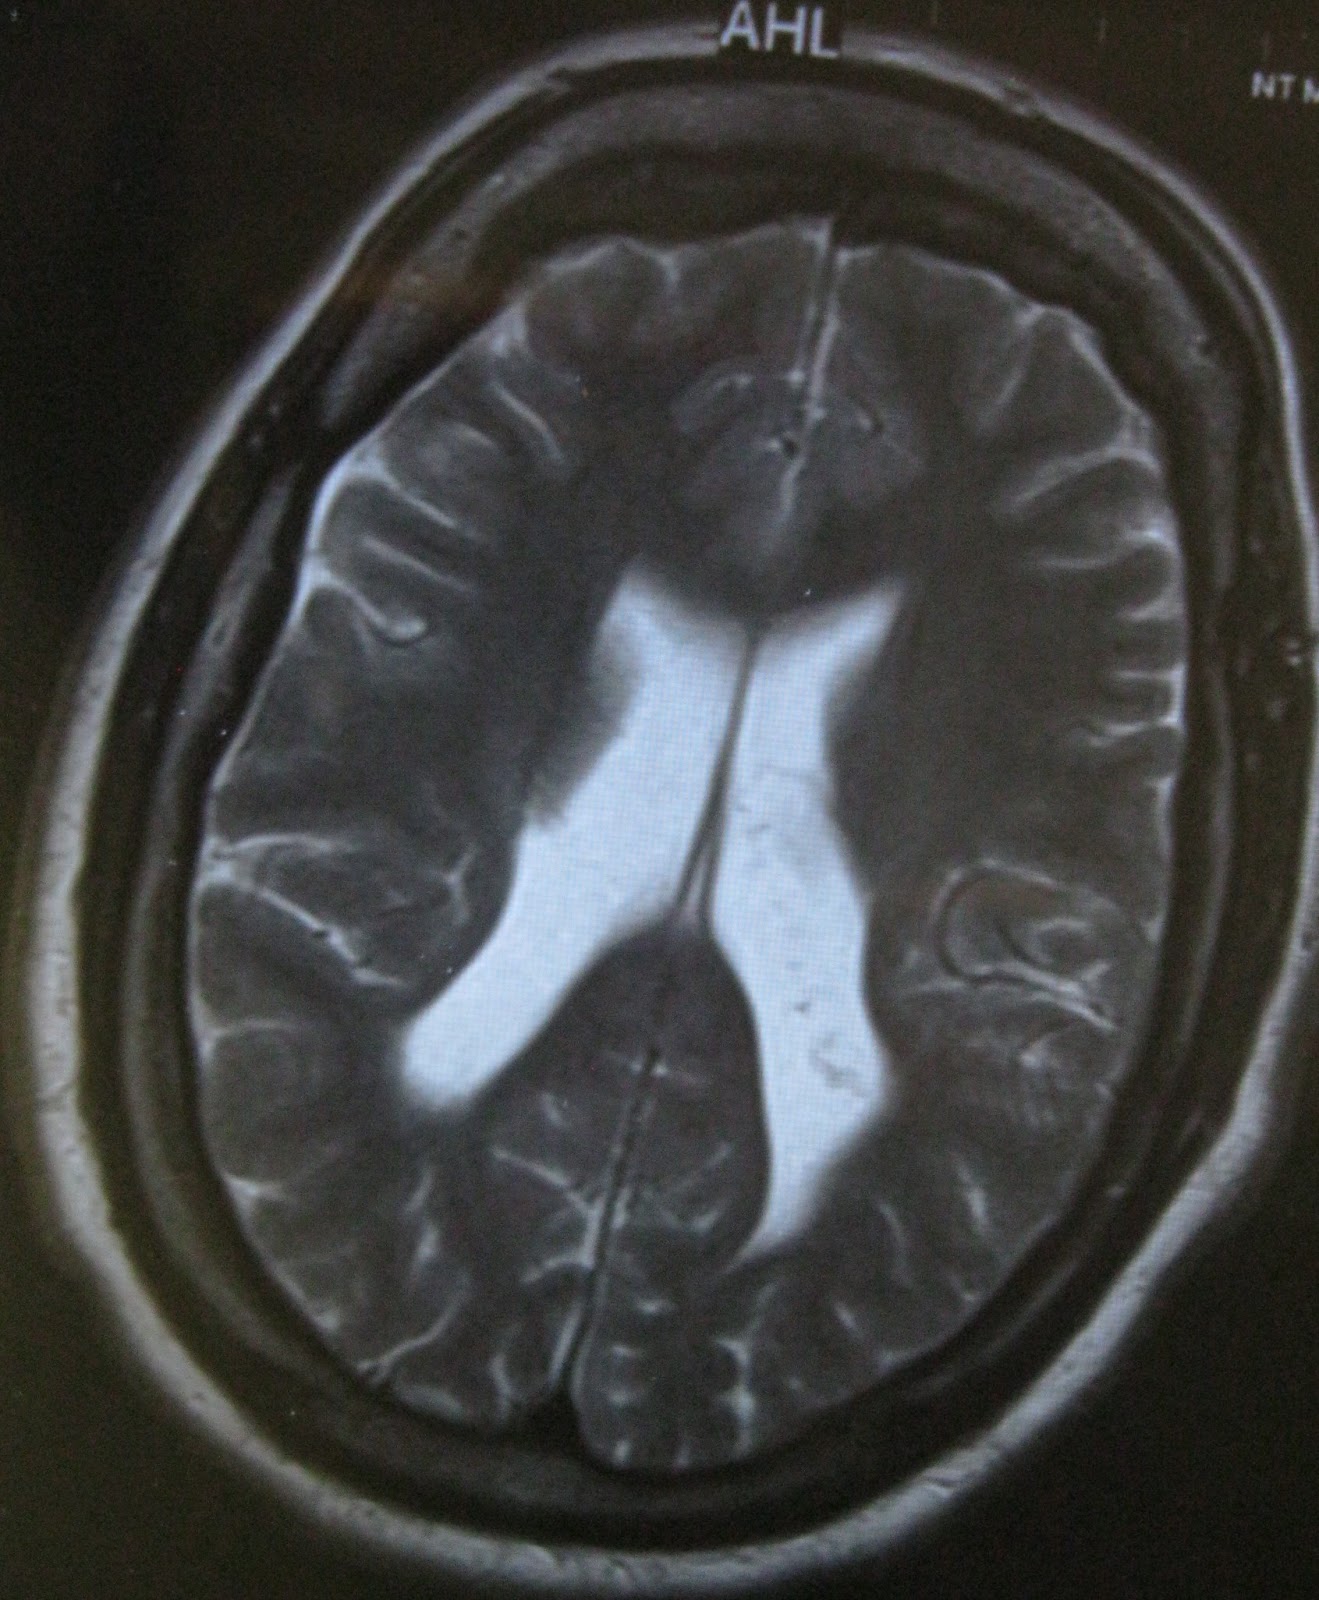

This...

...to this in seven days.